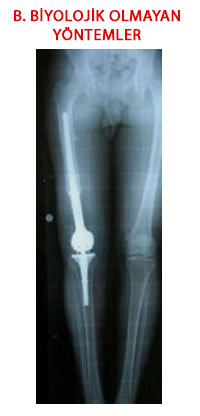

Nonbiyolojik Rekonstrüksiyon ve Yöntemleri

Tümör çıkartıldıktan sonra oluşan kemik ve eklem eksikliklerinin doğal olmayan, değişim göstermeyen ve hiçbir zaman vücudun kendi dokusuna dönüşmeyecek malzemeler kullanılarak giderilmesidir. Amaç eksikleri tamamlamanın yanında vücut bölümünün hemen kullanılabilir hale getirilmesidir. Bu malzemeler hemen bulunabilir ve günümüzdeki çeşitlilikleri sayesinde her tür boy, şekil ve bölge için mevcutturlar. Buna karşılık en önemli sorunları vücudun kendi dokusuna dönüşemedikleri için uzun dönem kullanımda canlı ve değişken doku ile bağlantı noktalarında ve kendi içlerinde gevşeme, aşınma, kırılma gibi problemlerin ortaya çıkmasıdır.

3.Metal Endoprotezler:

Ekstremite koruyucu cerrahi alanında çığır açan yöntemlerdir.

Protezler sayesinde eklem yüzeyleri ve ekleme komşu kemik bölümlerinin feda edildiği hastalarda hareketli bir eklem sağlanabilmektedir. Protezler çıkartılan kemik ve eklem bölümlerini taklit eden yapıda metal ve eklem yüzeylerinin esnekliğini sağlayan plastik parçalardan oluşurlar. Kemiğe kemik çimentosu ya da zaman içinde kemik ile kaynaşan özel yüzey yapılarıyla bağlanırlar.

Tümör çıkartılırken vücut yüklerini üzerine alan ve dengeli bir dağılımı sağlayan önemli adale grupları ve bağlar da çıkartılmak zorunda kalınabilmektedir. Bu nedenle tümör tedavisinde kullanılan protezler doğal eklem işleyişinden biraz daha farklı çalışırlar. Eklemde esas hareket menteşe şeklinde tek yöndedir. Başlangıçta sadece bu yönde harekete izin veren modellerde gevşeme ,aşınma ve kırılma problemlerinin fazlalığı nedeniyle bu problemleri önemli ölçüde çözen yeni modeller geliştirilmiştir. Yeni dönem protezler ilaveten kısıtlı bir dönme hareketine izin vermekte ve kemiğe çimentosuz yöntemle tesbit edilmektedirler. Ancak tüm tümör protezlerinde kemik bağlantı noktalarındaki sap bölümleri ve eklem bağlantı bölümleri anormal ve aşırı yüklenmektedir. Hastalar genelde genç, aktif ve yaşam beklentisi uzun insanlardır. Bu nedenle zaman içinde kırılma, gevşeme ve aşınmaya bağlı sorunlar ve bunların revizyonları beklenmelidir.

İlk geliştirildiklerinde kişiye özel yapıldıkları için hazır hale gelmeleri uzun bir zaman gerektirirken günümüzde omuzdan ayak bileğine kadar tüm eklem bölümlerini ve bunların birbirleri ile bağlantılarını aynı anda bir araya getirebilecek teknoloji geliştirilmiştir. Bunlar birbirine bağlanabilen değişik boylarda hazır ve her an el altında bulunabilen parçalardır.